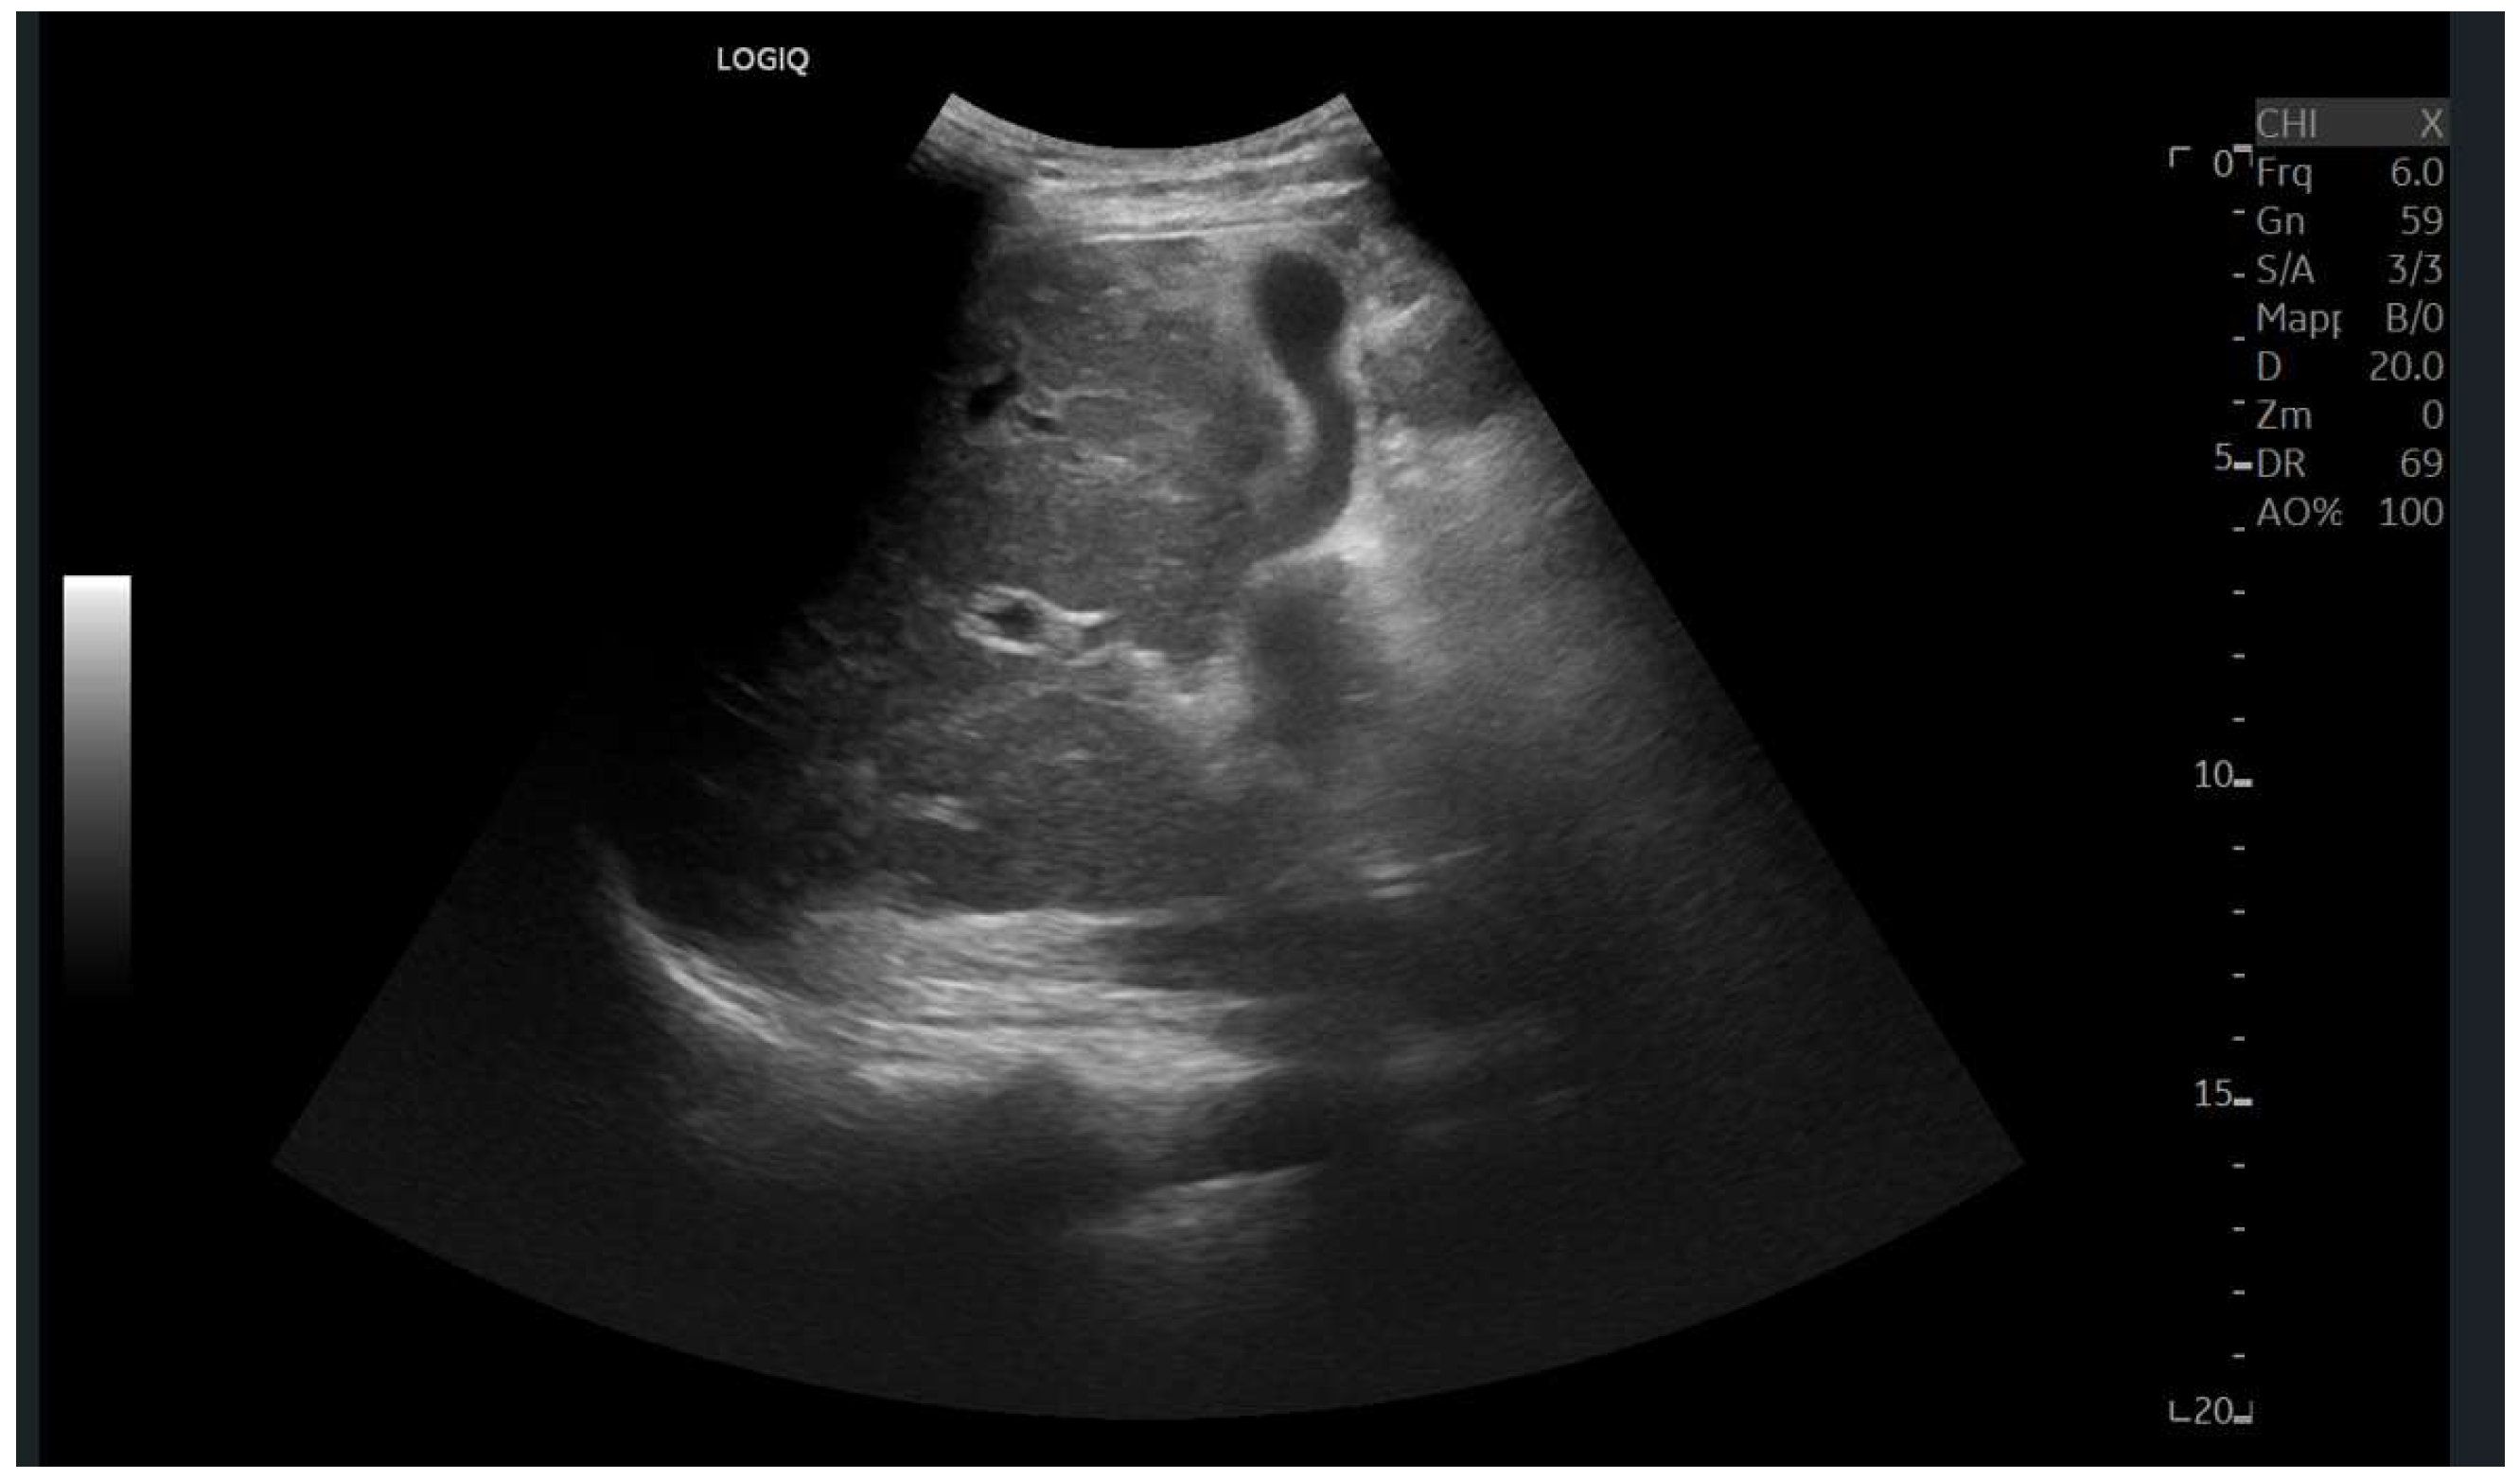

Ultrasound imaging is capable of identifying heterogeneous echotexture and hepatomegaly, which are early indicators of congestive hepatopathy [46]. Several studies have shown correlations between the extent of sonographic abnormalities and the severity of hepatic fibrosis or cirrhosis [36,47,48]. The most common ultrasound findings encompass a nodular hepatic surface, right-lobe volume reduction, smooth-to-rounded contour changes, and irregular outer profiles [49,50,51] (Figure 2). The echotexture appears granular and markedly heterogeneous, with hyperechogenic nodules of varying sizes [49,50,51] (Figure 3, Figure 4, Figure 5, Figure 6, Figure 7 and Figure 8).

Figure 2.

Detail with convex probe in oblique subcostal scan: note the rounded margins, the heterogeneous echotexture, particularly in the left segments, and a marked hypotrophy of the right lobe.

Figure 3.

Subcostal scan with convex probe showing symmetrical thickening of the gallbladder walls, consistent with congestion.

Figure 4.

Oblique subcostal scan with convex probe showing diffuse periportal edema.